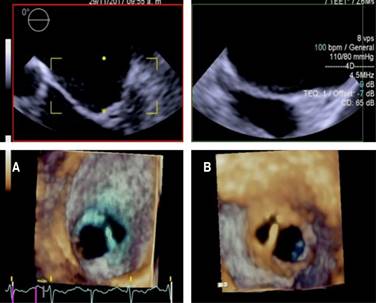

Figure 2: 2D transesophageal echocardiography at the mild esophageal projection at 57o showing the bicuspid aortic valve.

Figure 3: Real-time 3D transesophageal echocardiography of A atrial face and B ventricular face. It is an eccentric type of double port mitral valve with a larger main port and a smaller accessory port located at the anterolateral commissure.